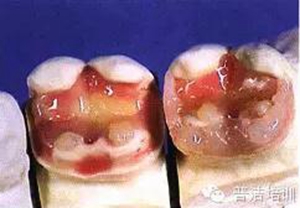

九、準(zhǔn)備口內(nèi)戴入

十、試戴樹(shù)脂高嵌體

十一、分開(kāi)粘結(jié),用聚四氟乙烯保護(hù)修復(fù)好的牙齒

十二、洞內(nèi)置入粘結(jié)水門(mén)汀,將高嵌體就位

十三、用器械使修復(fù)體完全就位

十四、完全就位前去除多余的水門(mén)汀,并用牙線和探針仔細(xì)去除牙齒之間的多余材料。

十五、修正、拋光

十六、最終的修復(fù)體,是不是很漂亮

修復(fù)后一周復(fù)查